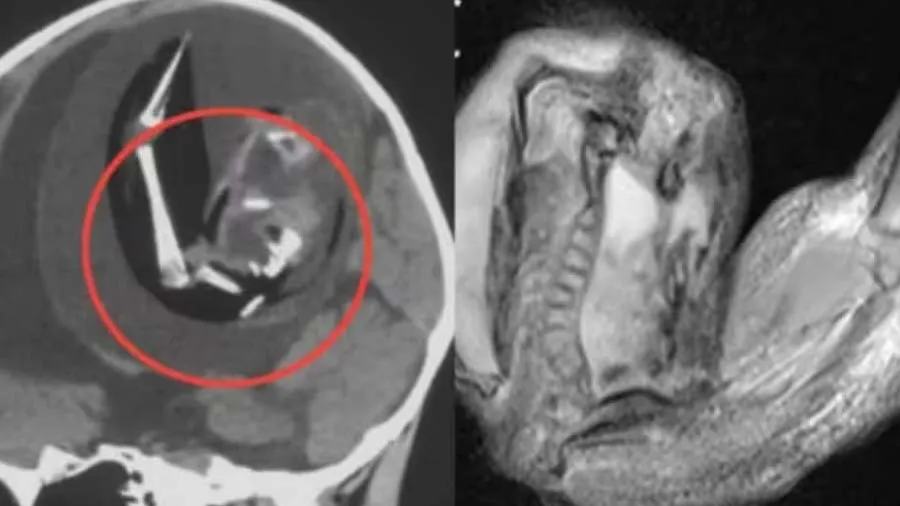

અહીં તમને જણાવી દઈએ કે, આ બાળકીનો જન્મ એક વર્ષ પહેલા થયો હતો, જન્મથી જ બાળકીના માથાની સાઈઝ સતત વધવા લાગી હતી. આવી સ્થિતિમાં બાળકીના માતા-પિતા તેને હોસ્પિટલ લઈ ગયા, જ્યાં તેનું સીટી સ્કેન કરવામાં આવ્યું. તપાસ બાદ ડોકટરોને જાણવા મળ્યું કે, બાળકીના મગજની અંદર ગર્ભ છે. ડૉક્ટરોએ જણાવ્યું કે, આ અજાત ભ્રૂણ બાળકના મગજમાં 4 ઈંચ જેટલો મોટો થઈ ગયો હતો અને તેની કમર, હાડકાં અને આંગળીના નખ પણ વિકસિત થઈ રહ્યા હતા. ડૉક્ટરોએ જણાવ્યું કે બાળક જ્યારે માતાના ગર્ભમાં હતો ત્યારથી જ આ અજાત ભ્રૂણનો વિકાસ બાળકના મગજની અંદર થઈ રહ્યો હતો.

બાળકીના મગજમાંથી કાઢવામાં આવેલા આ ગર્ભના જીનોમ સિક્વન્સિંગમાં જાણવા મળ્યું કે આ ગર્ભ આ બાળકીનો જોડિયા છે. મેડિકલ સાયન્સમાં આ સ્થિતિને ગર્ભમાં ગર્ભ કહેવાય છે. આ સ્થિતિમાં, માતાના ગર્ભાશયમાં ઉગતા બે ભ્રૂણમાંથી, એક ગર્ભ બીજા ગર્ભની અંદર વિકાસ કરવાનું શરૂ કરે છે. આવું ત્યારે થાય છે જ્યારે બે ભ્રૂણ યોગ્ય રીતે અલગ થતા નથી.